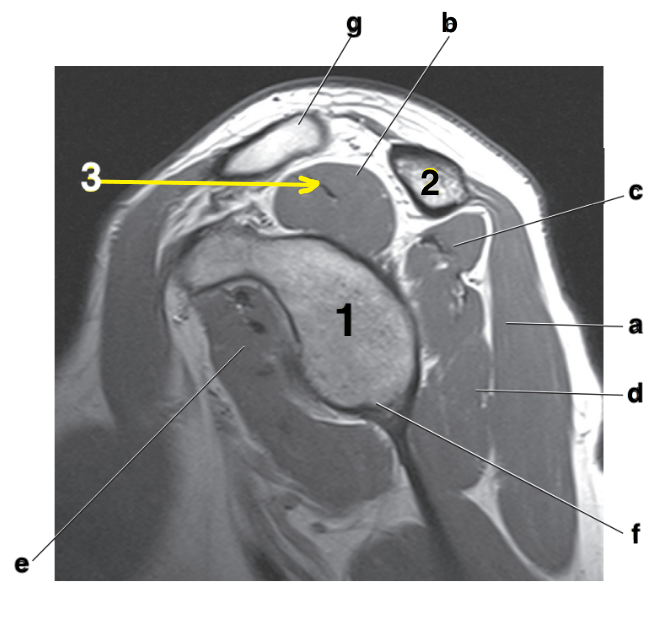

Acromion

Scapular spine

Supraspinatus tendon

Supraspinatus muscle

Posterior glenoid labrum

f